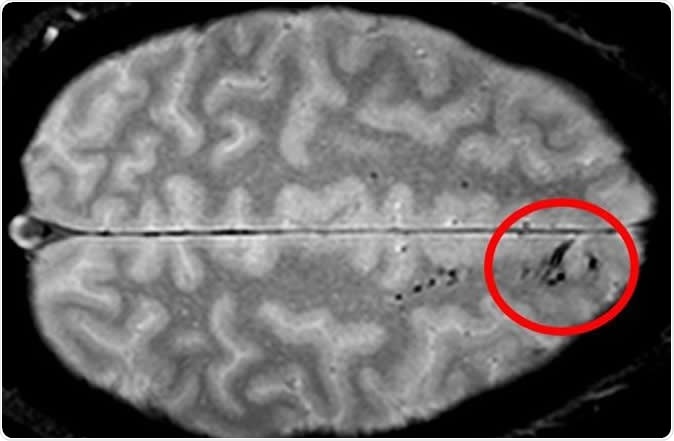

Traumatic microbleeds appear as dark lesions on MRI scans and suggest damage to brain blood vessels after head injury. Image Credit: Latour Lab/NINDS.

Microbleeds are small areas of hemorrhage that are not detectable by CT scanning but are picked up by MRI as tiny dark patches. They are caused by blood vessel injury, and may be found after apparently even minor degrees of head injury. The problems caused by this type of damage to blood vessels is not quite clear but since any injury to brain cells can be potentially wide in its impact, the researchers feel that microbleeds need to be studied in greater depth.

The findings showed that microbleeds were present on the MRI scan in 31% of all the patients, but the frequency varied with the severity of head injury. For instance, when severe head injury was present, almost 60% of the patients had microbleeds, in contrast with only 27% in mild injury.

The appearance of the microbleeds was also variable – some were linear, while others were punctate (like small dots), and most patients showed both types. The area of the brain most likely to show microbleeds was the frontal region of both hemispheres.